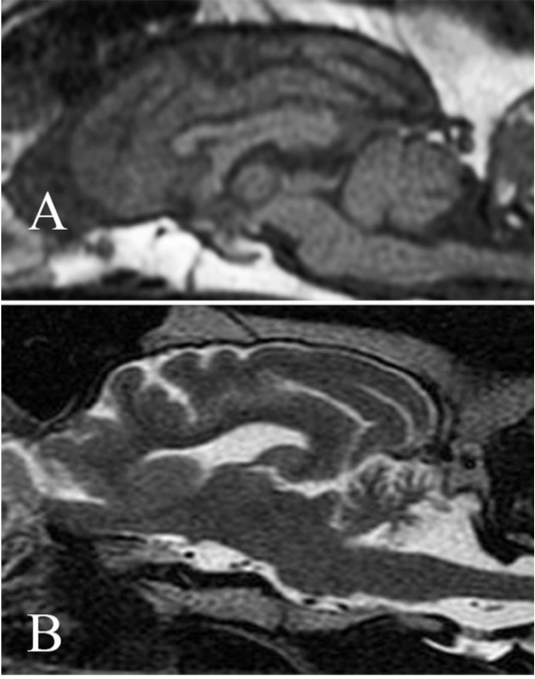

UCDavis dog MRI.jpg